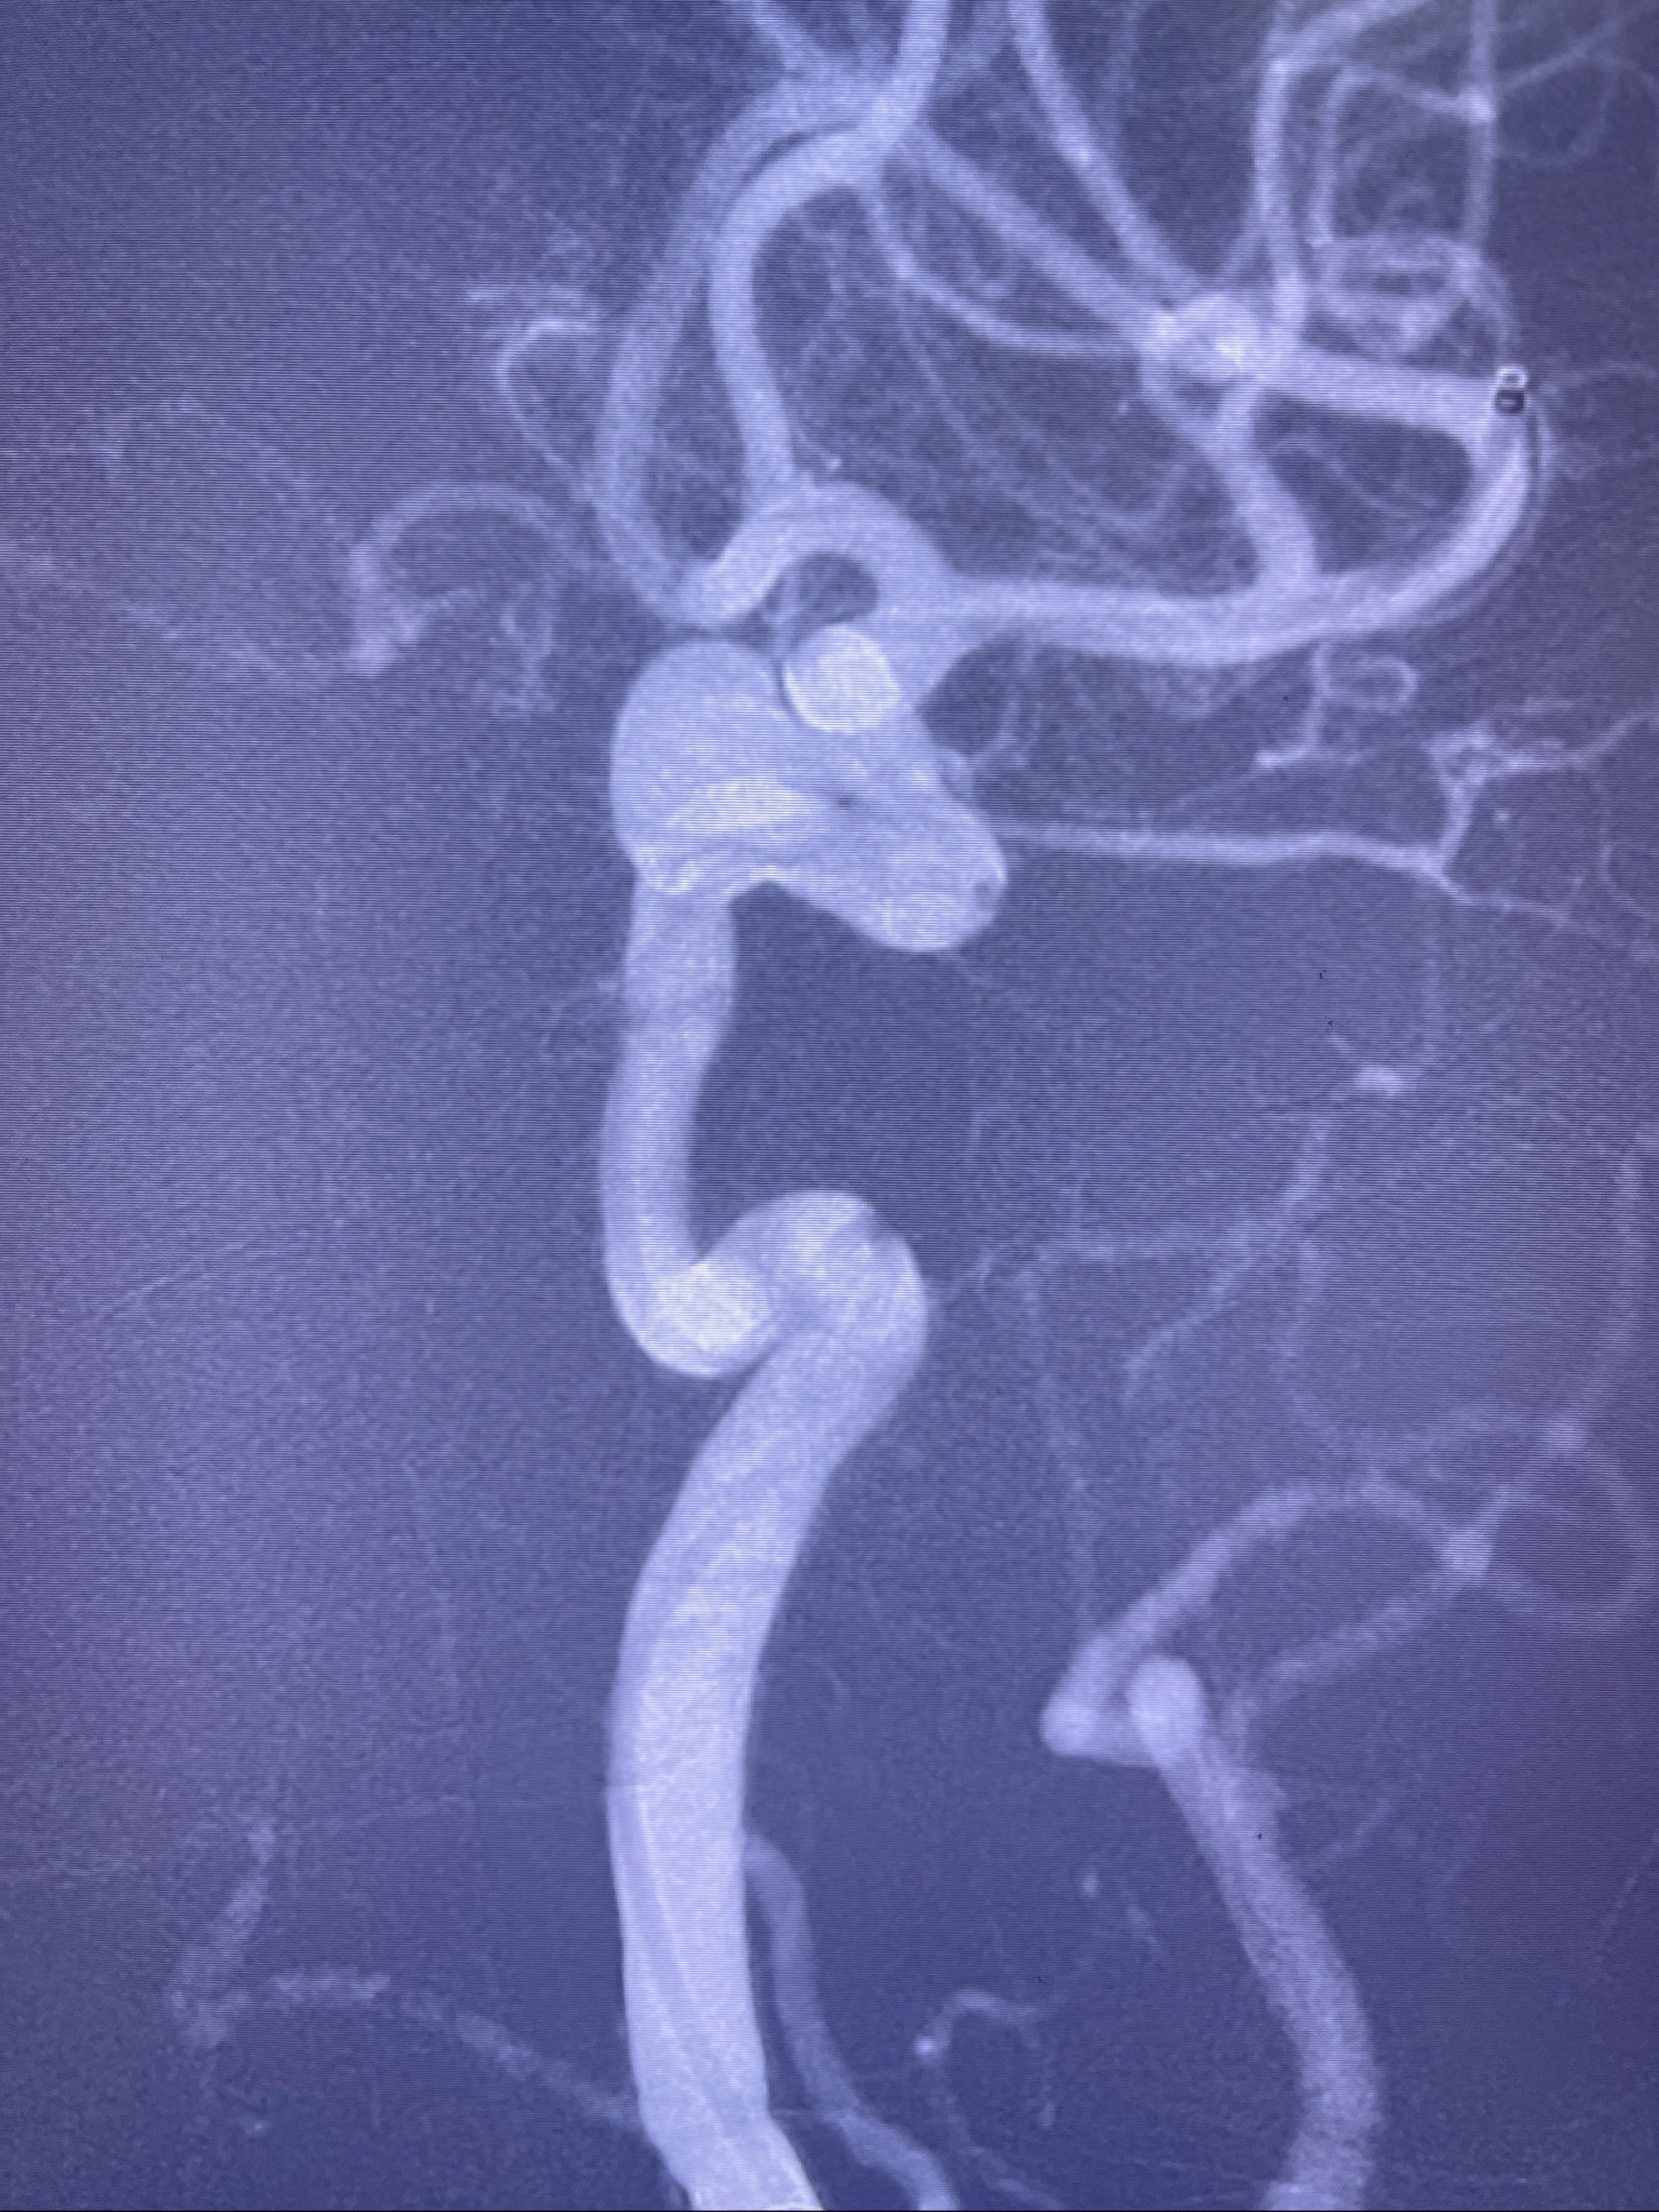

2023-08-30DSA:左侧颈内动脉眼动脉动脉瘤,约3*9.2*7.3mm大小

2023-09-04术前增强MRI